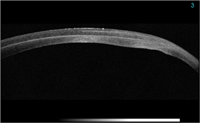

Figura 1). También se pueden estudiar adelgazamientos corneales como el queratocono (

Figura 2), opacidades corneales estromales y su profundidad, patologías asociadas al LASIK (

Figura 2. Vemos la ectasia de un queratocono.